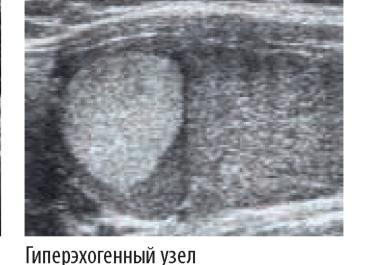

В результате обследования все узлы щитовидной железы подразделяются на три основных вида: гипоэхогенные, изоэхогенные и гиперэхогенные.

Гиперэхогенный

Наблюдается в том случае, когда его эхогенность намного выше окружающей ткани.

- Гиперэхогенное образование – это зона повышенной акустической плотности. Она связана с преобладанием соединительной ткани в железе и отложением солей кальция.